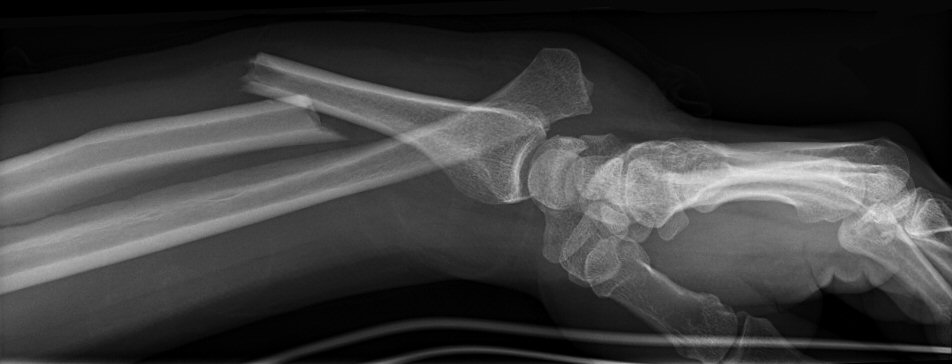

Galeazzifraktur: fraktur på distala tredjedelen av radius och samtidig luxation av ulnahuvudet (vid DRU-leden).

Galeazzifraktur